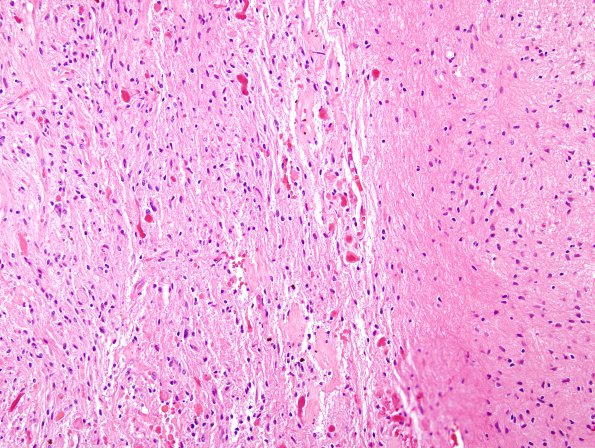

44B2 Astrocytoma, pilocytic (Case 44) H&E 4

Sharp margin with the surrounding brain (H&E)